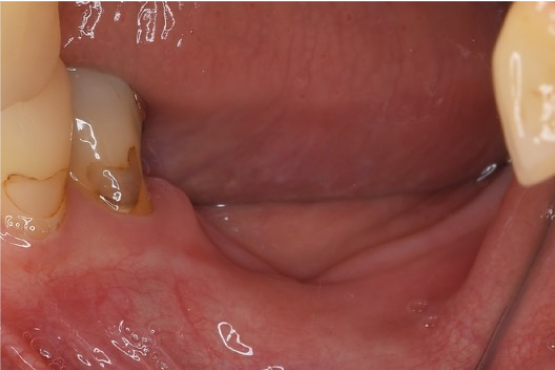

症例2

| 項目 | 詳細 |

|---|---|

| 患者様データ | 50代 女性 |

| 来院時の主訴 | 「健康的に噛めるようになりたい。」 |

| 医院の診断 | 歯牙欠損、角化歯肉不足 |

| 通院期間 | 10か月 |

| 来院回数 | 15回 |

| 治療費 | 総額:900,000円(税抜) 【内訳】 GBR(骨再生手術)250,000円、インプラント埋入手術250,000円、2次手術+FGG(遊離歯肉移植術)55,000+60,000円、仮歯30,000円、インプラント上部構造(セラミッククラウン)170,000円、セラミックオーバーレイ85,000円 |

| リスクと副作用 | 定期的なメンテナンスが必要、術後若干の腫れと痛み |

| ここがこだわりのポイント!☝ | ただ噛めるだけではなく、歯ブラシに対して抵抗できる健常な歯肉も再生させる処置を行うことで、 長期間メインテナンスしやすい環境づくりをしています。 |